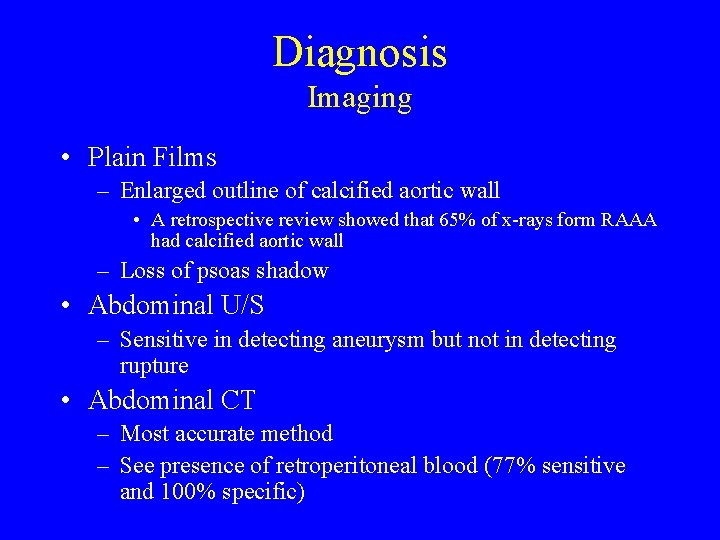

Diagnosis Imaging • Plain Films – Enlarged outline of calcified aortic wall • A retrospective review showed that 65% of x-rays form RAAA had calcified aortic wall – Loss of psoas shadow • Abdominal U/S – Sensitive in detecting aneurysm but not in detecting rupture • Abdominal CT – Most accurate method – See presence of retroperitoneal blood (77% sensitive and 100% specific)